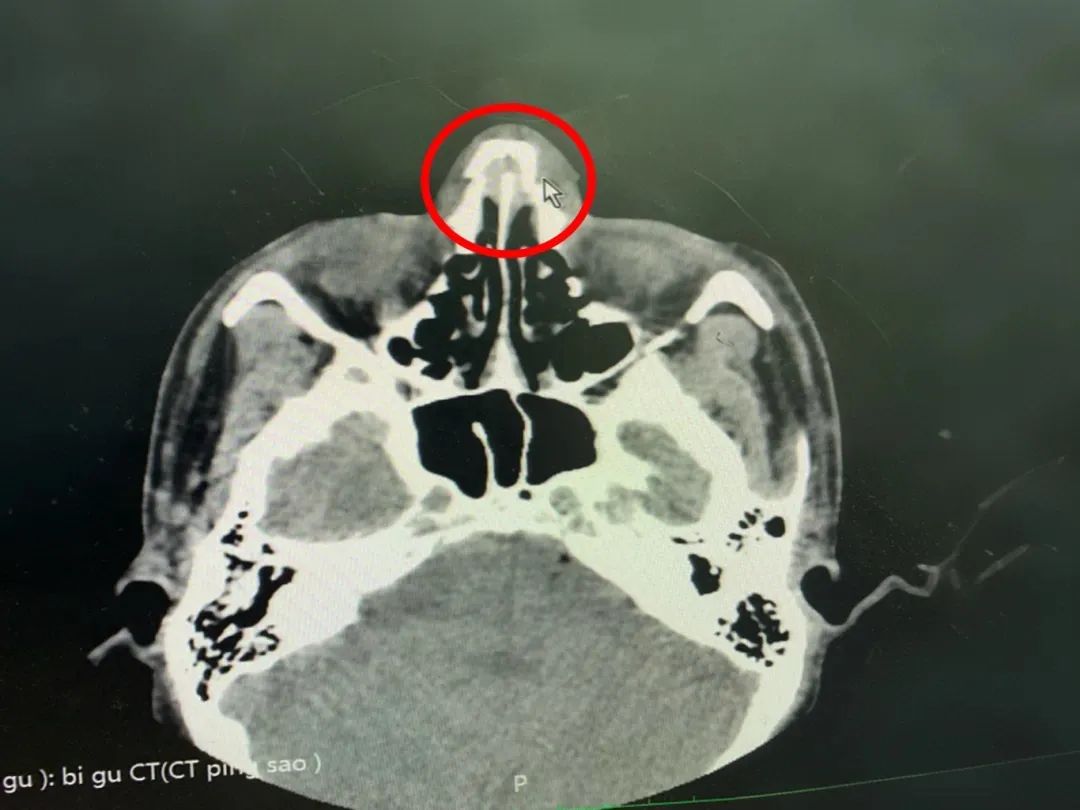

醫生通過CT檢查顯示:雙側鼻骨骨折,斷端錯位,周圍軟組織稍腫脹,正如醫生猜測的那樣,確診:“鼻骨骨折”。